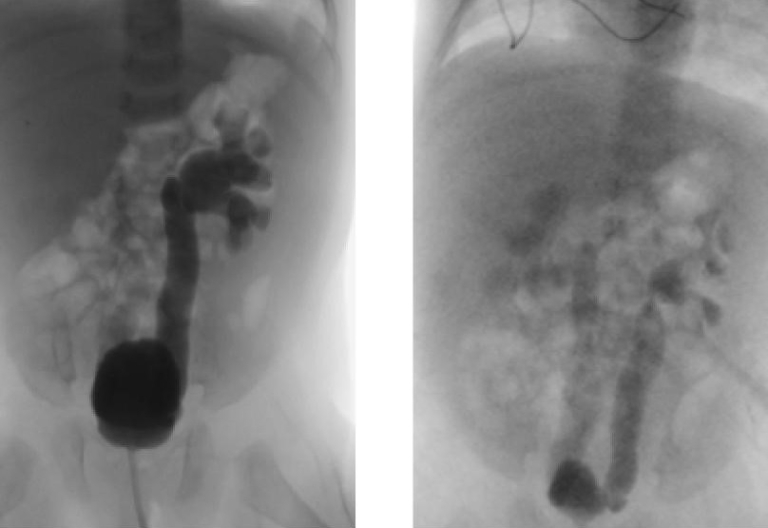

- Dimercaptosuccinic Acid (DMSA) Renal Scan (Figure 2) This is a nuclear medicine test, and should not be used routinely after a first febrile UTI, but may be helpful in identifying renal scarring later on. This test will show both renal scarring and active pyelonephritis, but cannot differentiate between the two entities. When evaluating for renal scarring, DMSA scan should not be obtained until four to six months from the time of acute pyelonephritis.8